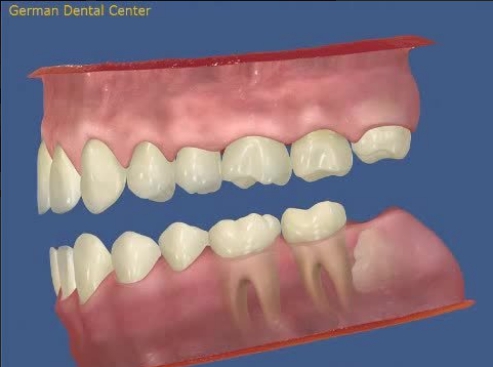

- Исправление прикуса